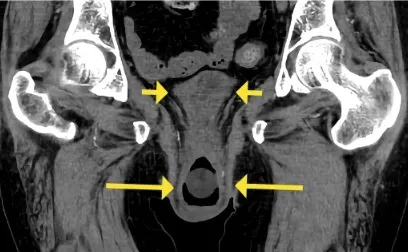

IRA + Icterícia: Um Caso que Exige Investigação Detalhada